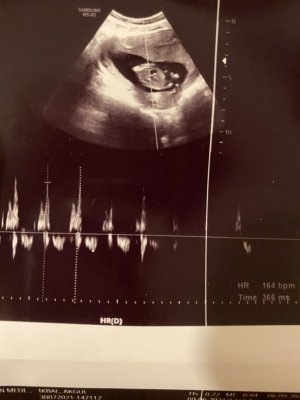

Merhabalar… görseldeki ultrason resimleri 12+5 olan ama bebek göstermedi fazla hareket etmediği için doktorum cinsiyetini göremedi. Şuan 16+3’üz haftaya randevum var ama ben meraktan çatlıyorum. Bazıları göğüs ucunun kararmasından,bazıları basenlerden ve karnın sivri olup yaygın olmasından yada kese şeklinden vs. anlıyorlar ( yorum yapıyolar). O kadar bekledim tabikide bir hafta daha beklerim ama çevremdekiler o kadar değişik yorum yapıyolar ki cidden benimde merakım artıyor artık…Aranızda yorum yapabilen varsa yapabilir mi?? Sizce cinsiyeti nedir?  bu arada Rabbim isteyen herkese en sağlıklısından ve hayırlısından evlat nasip etsin

Kimler kimler yazdı?Kız gibiMerhabalar… görseldeki ultrason resimleri 12+5 olan ama bebek göstermedi fazla hareket etmediği için doktorum cinsiyetini göremedi. Şuan 16+3’üz haftaya randevum var ama ben meraktan çatlıyorum. Bazıları göğüs ucunun kararmasından,bazıları basenlerden ve karnın sivri olup yaygın olmasından yada kese şeklinden vs. anlıyorlar ( yorum yapıyolar). O kadar bekledim tabikide bir hafta daha beklerim ama çevremdekiler o kadar değişik yorum yapıyolar ki cidden benimde merakım artıyor artık…Aranızda yorum yapabilen varsa yapabilir mi?? Sizce cinsiyeti nedir?bu arada Rabbim isteyen herkese en sağlıklısından ve hayırlısından evlat nasip etsin

Benim doktorum tam 12.haftaya girmemişti kız dedi sonra tekrar gittiğimizde de kız dedi. Demek ki doktordan doktora fark var. Vallahi ben hiç anlamıyorum bu cinsiyet işlerinden. Ama içime hep kız doğuyordu çok şükür kız olduMerhabalar… görseldeki ultrason resimleri 12+5 olan ama bebek göstermedi fazla hareket etmediği için doktorum cinsiyetini göremedi. Şuan 16+3’üz haftaya randevum var ama ben meraktan çatlıyorum. Bazıları göğüs ucunun kararmasından,bazıları basenlerden ve karnın sivri olup yaygın olmasından yada kese şeklinden vs. anlıyorlar ( yorum yapıyolar). O kadar bekledim tabikide bir hafta daha beklerim ama çevremdekiler o kadar değişik yorum yapıyolar ki cidden benimde merakım artıyor artık…Aranızda yorum yapabilen varsa yapabilir mi?? Sizce cinsiyeti nedir?bu arada Rabbim isteyen herkese en sağlıklısından ve hayırlısından evlat nasip etsin

Merhabalar… görseldeki ultrason resimleri 12+5 olan ama bebek göstermedi fazla hareket etmediği için doktorum cinsiyetini göremedi. Şuan 16+3’üz haftaya randevum var ama ben meraktan çatlıyorum. Bazıları göğüs ucunun kararmasından,bazıları basenlerden ve karnın sivri olup yaygın olmasından yada kese şeklinden vs. anlıyorlar ( yorum yapıyolar). O kadar bekledim tabikide bir hafta daha beklerim ama çevremdekiler o kadar değişik yorum yapıyolar ki cidden benimde merakım artıyor artık…Aranızda yorum yapabilen varsa yapabilir mi?? Sizce cinsiyeti nedir?bu arada Rabbim isteyen herkese en sağlıklısından ve hayırlısından evlat nasip etsin

Bana da yorum yapan arkadaşlar olur mu 14 haftalık bebeğim doktor erkek gıbı dedi ama emin olamadım bende sizede sormak istedimMerhabalar… görseldeki ultrason resimleri 12+5 olan ama bebek göstermedi fazla hareket etmediği için doktorum cinsiyetini göremedi. Şuan 16+3’üz haftaya randevum var ama ben meraktan çatlıyorum. Bazıları göğüs ucunun kararmasından,bazıları basenlerden ve karnın sivri olup yaygın olmasından yada kese şeklinden vs. anlıyorlar ( yorum yapıyolar). O kadar bekledim tabikide bir hafta daha beklerim ama çevremdekiler o kadar değişik yorum yapıyolar ki cidden benimde merakım artıyor artık…Aranızda yorum yapabilen varsa yapabilir mi?? Sizce cinsiyeti nedir?bu arada Rabbim isteyen herkese en sağlıklısından ve hayırlısından evlat nasip etsin